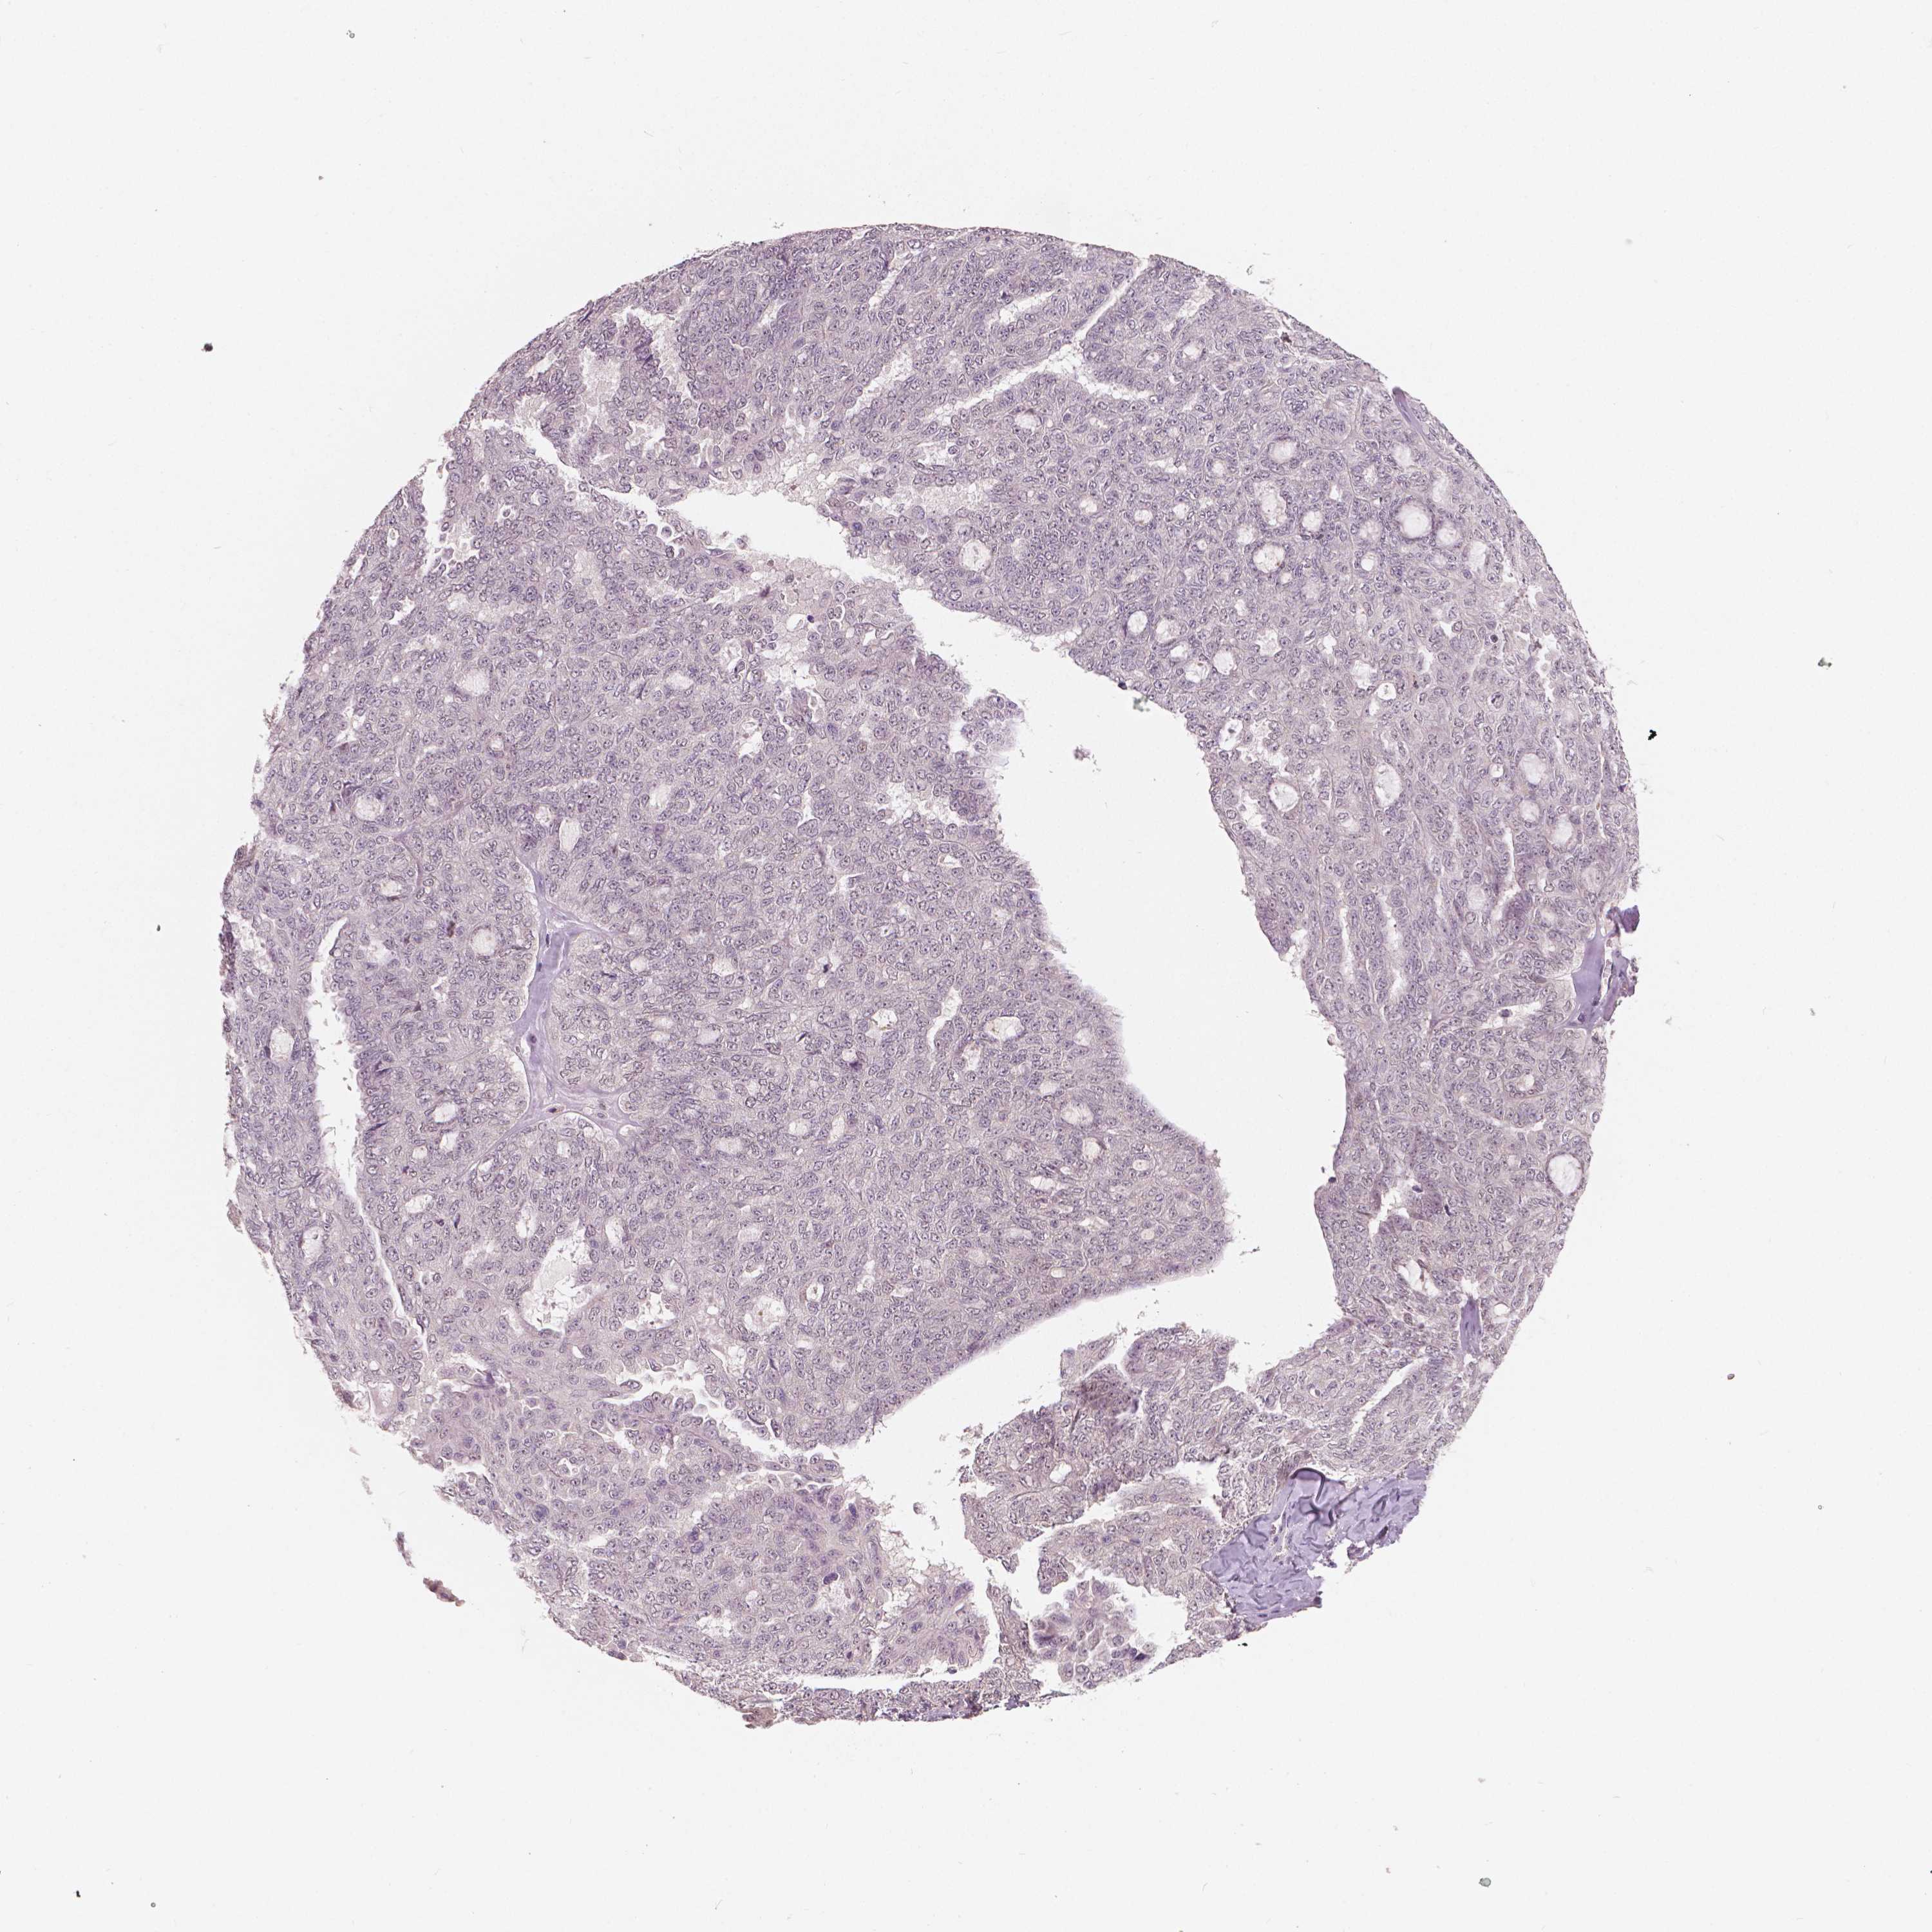

OVARIAN CANCER - Protein expressioni

A mouse-over function shows sample information and annotation data. Click on an image to view it in a full screen mode. Samples can be filtered based on level of antibody staining by selecting one or several of the following categories: high, medium, low and not detected. The assay and annotation is described here.

Note that samples used for immunohistochemistry by the Human Protein Atlas do not correspond to samples in the TCGA dataset.

Antibody stainingi

Antibody staining in the annotated cell types in the current human tissue is reported as not detected, low, medium, or high, based on conventional immunohistochemistry profiling in selected tissues. This score is based on the combination of the staining intensity and fraction of stained cells.

Each image is clickable and will lead to virtual microscopy that enables deeper exploration of all samples and also displays staining intensity scores, fraction scores and subcellular localization as well as patient and tissue information for each sample.

Antibody HPA015801

Antibody CAB068246

Antibody CAB068247

Staining

High

Medium

Low

Not detected

Cystadenocarcinoma, serous, NOS

Cystadenocarcinoma, mucinous, NOS

Carcinoma, endometroid